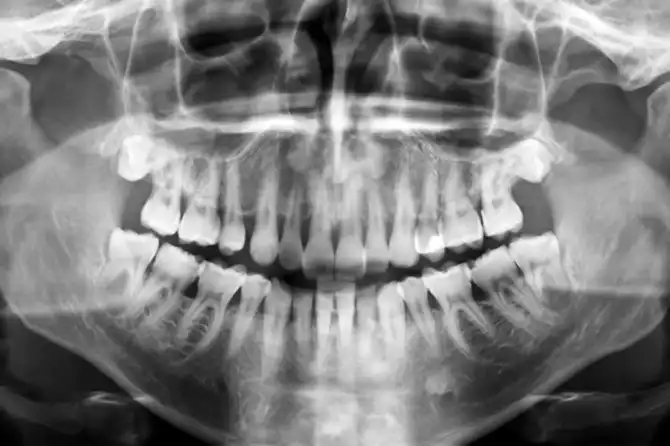

Многие считают, что эффект плацебо вызывает исключительно психологические изменения. Тем не менее есть убедительные доказательства физической реакции тела на прием ложных медикаментов. В 2005 году исследователи из Университета штата Мичиган выполняли сканирование мозга 14 здоровых молодых мужчин. Им в челюстную полость вводили раствор, вызывавший боль. Вскоре пациентам давали плацебо, называя его эффективным обезболивающим. В ходе сканирования исследователи увидели, что области мозга, отвечающие за выработку эндорфинов (гормонов удовольствия), активизировались. Участники также заявляли, что боль утихла, несмотря на то, что никаких объективных предпосылок к этому не было.

После приема плацебо пациенты перестали чувствовать боль в челюсти

Это интересно: в ходе схожего эксперимента, проведенного в 2001 году, участникам давали плацебо и дополнительно вводили препараты, блокирующие выработку эндорфинов в организме. Результат был неожиданным: на этот раз эффект плацебо не сработал. Эти два исследования позволяют сделать вывод, что именно от эндорфинов зависит, будет ли прием безвредных пилюль эффективным.